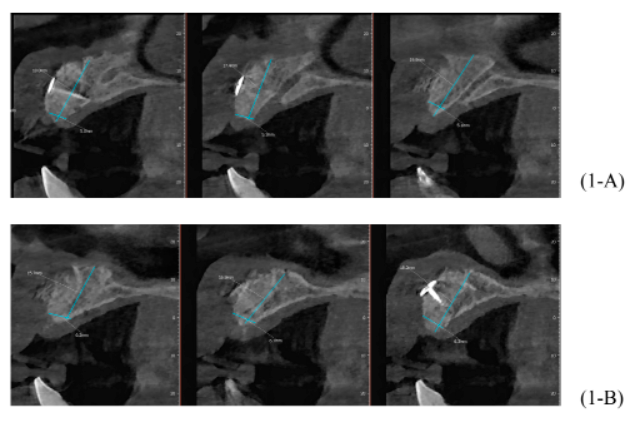

Após oito meses, foi realizada outra tomografia computadorizada (TC) na própria clínica escola, onde foram realizadas medidas de altura e espessura evidenciando grande ganho ósseo horizontal. Não ocorreu quaisquer tipo de complicação no pós-operatório tardio (imagens 1-A, 1-B, 1-C, 1-D).

Foram planejados três implantes do tipo Cone Morse Maestro Implacil De Bortoli 3.5 x 13 mm. Após remoção de maneira facilitada dos parafusos tenda, foram instalados três implantes em ótimo posicionamento tridimensional (imagens 1-E, 1-F, 1-G, 1-H). Todos apresentaram estabilidade primária de 35 Ncm de torque e aguardamos quatro meses para posterior reabilitação protética definitiva com próteses individualizadas de metalocerâmica do tipo parafusada.